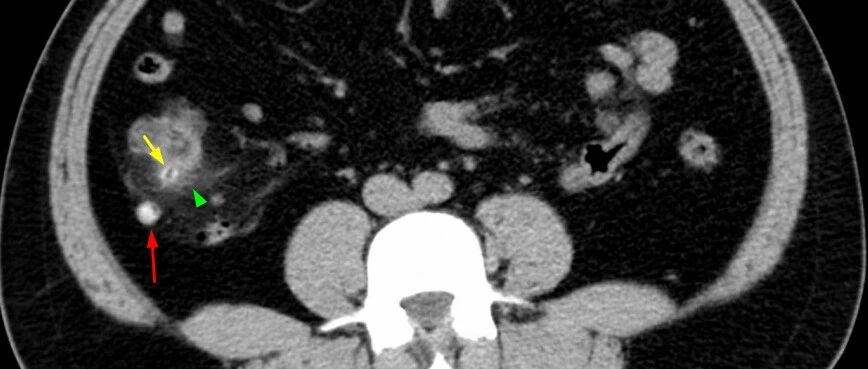

阑尾腺癌超声表现1例

病例

2024-06-06

阑尾黏液腺癌超声表现1例

2023-11-28